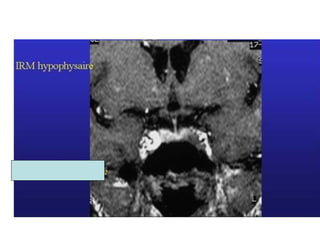

Mme P,  Cycle cortisol  158 µg/l  8h 216  12h 204  16h 217  20h CLU 120 µg/24h (<70) Freinage mn: cortisol plasmatique à 70 µg/l Cycle ACTH 54 ng/l 74 30 25